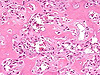

CASO N° 4 (Dr. Bonan e Dr. Roman)

Paciente do gênero masculino, 46 anos de idade, apresenta lesão no palato.